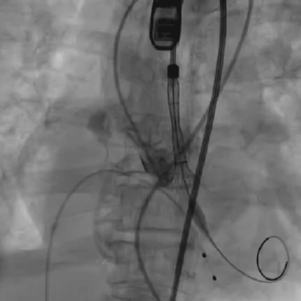

从三叶瓣重度钙化到二叶瓣畸形的根部解剖,从单纯主动脉瓣反流到入路极端迂曲挑战的案例。TaurusOne凭借其优异的柔顺性,支撑力强及内外层双侧裙边的特点,都能从容应对复杂的临床患者解剖结构。从患者的临床选择到术后的长久获益,从手术入路的种类到术中操作的注意事项,从围术期卒中的循证医学到术后的抗凝抗栓用药规范,在线专家共同交流彼此中心的围术期TAVR经验和分享现阶段经导管主动脉瓣置换的诊疗策略。针对当前TAVR领域多个热点学术问题进行了热烈的讨论,现场可谓精彩纷呈、高潮迭起。专家们纷纷借此契机相互交流探讨,分享各自的单中心经验,力求进一步提升TAVR手术的安全性和有效性,为主动脉瓣相关疾病的患者带来长远综合获益。